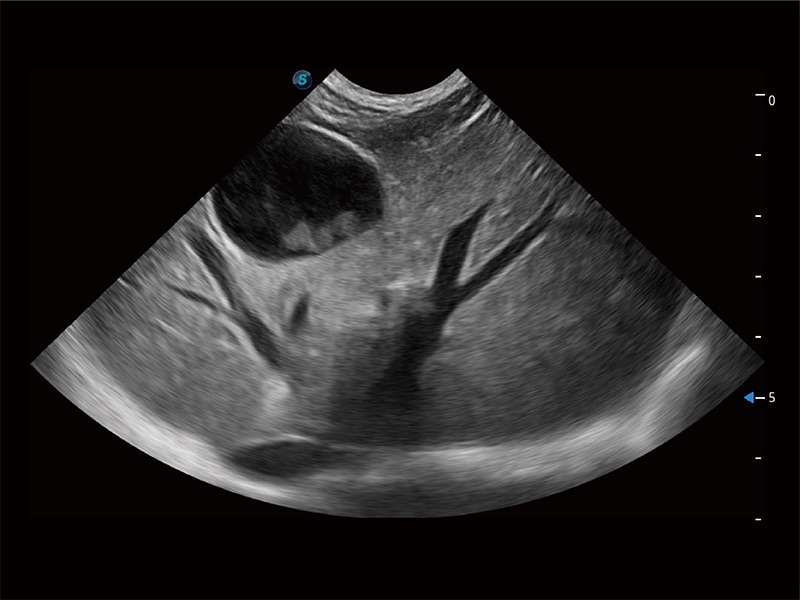

高性能和先进的临床应用工具可以为动物医生提供临床信心。ProPet 80 搭载了先进的腹部和浅表应用工具,帮助医生在日常临床实践中发挥前所未有的作用。

极大提升超低速微细血流的检出能力,同时更精准地滤除软组织和超声信号,为兽用医生提供以往无法通过常规血流获得的疾病诊断信息。

在传统二维血流成像的基础上,呈现血流的立体感,具有动感的生命力之美。即便是微小的血管也能轻松应对,提高了血流的视觉敏感性。

非线性融合造影成像充分利用谐波和基波信号,为难以观察的血流进行增强显像。可用于线阵、凸阵、微凸阵、相控阵探头。